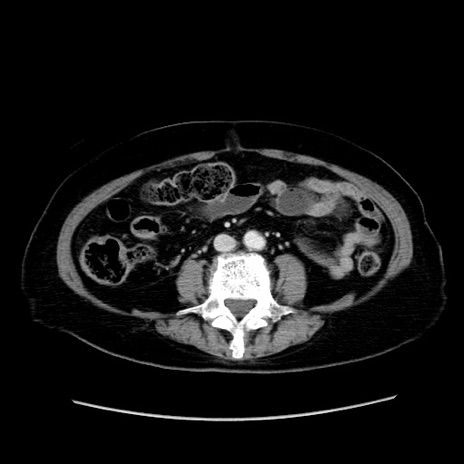

症例19(横断像)

【症例】80歳代女性

【主訴】下腹部痛

【現病歴】約8時間前より下腹部痛の出現あり、救急外来受診。

【既往歴】両側付属器切除

【身体所見】意識清明、下腹部正中に手術痕あり、その部位に一致して圧痛と反跳痛あり。腸蠕動音は亢進。

【データ】WBC 9300、CRP 0.15